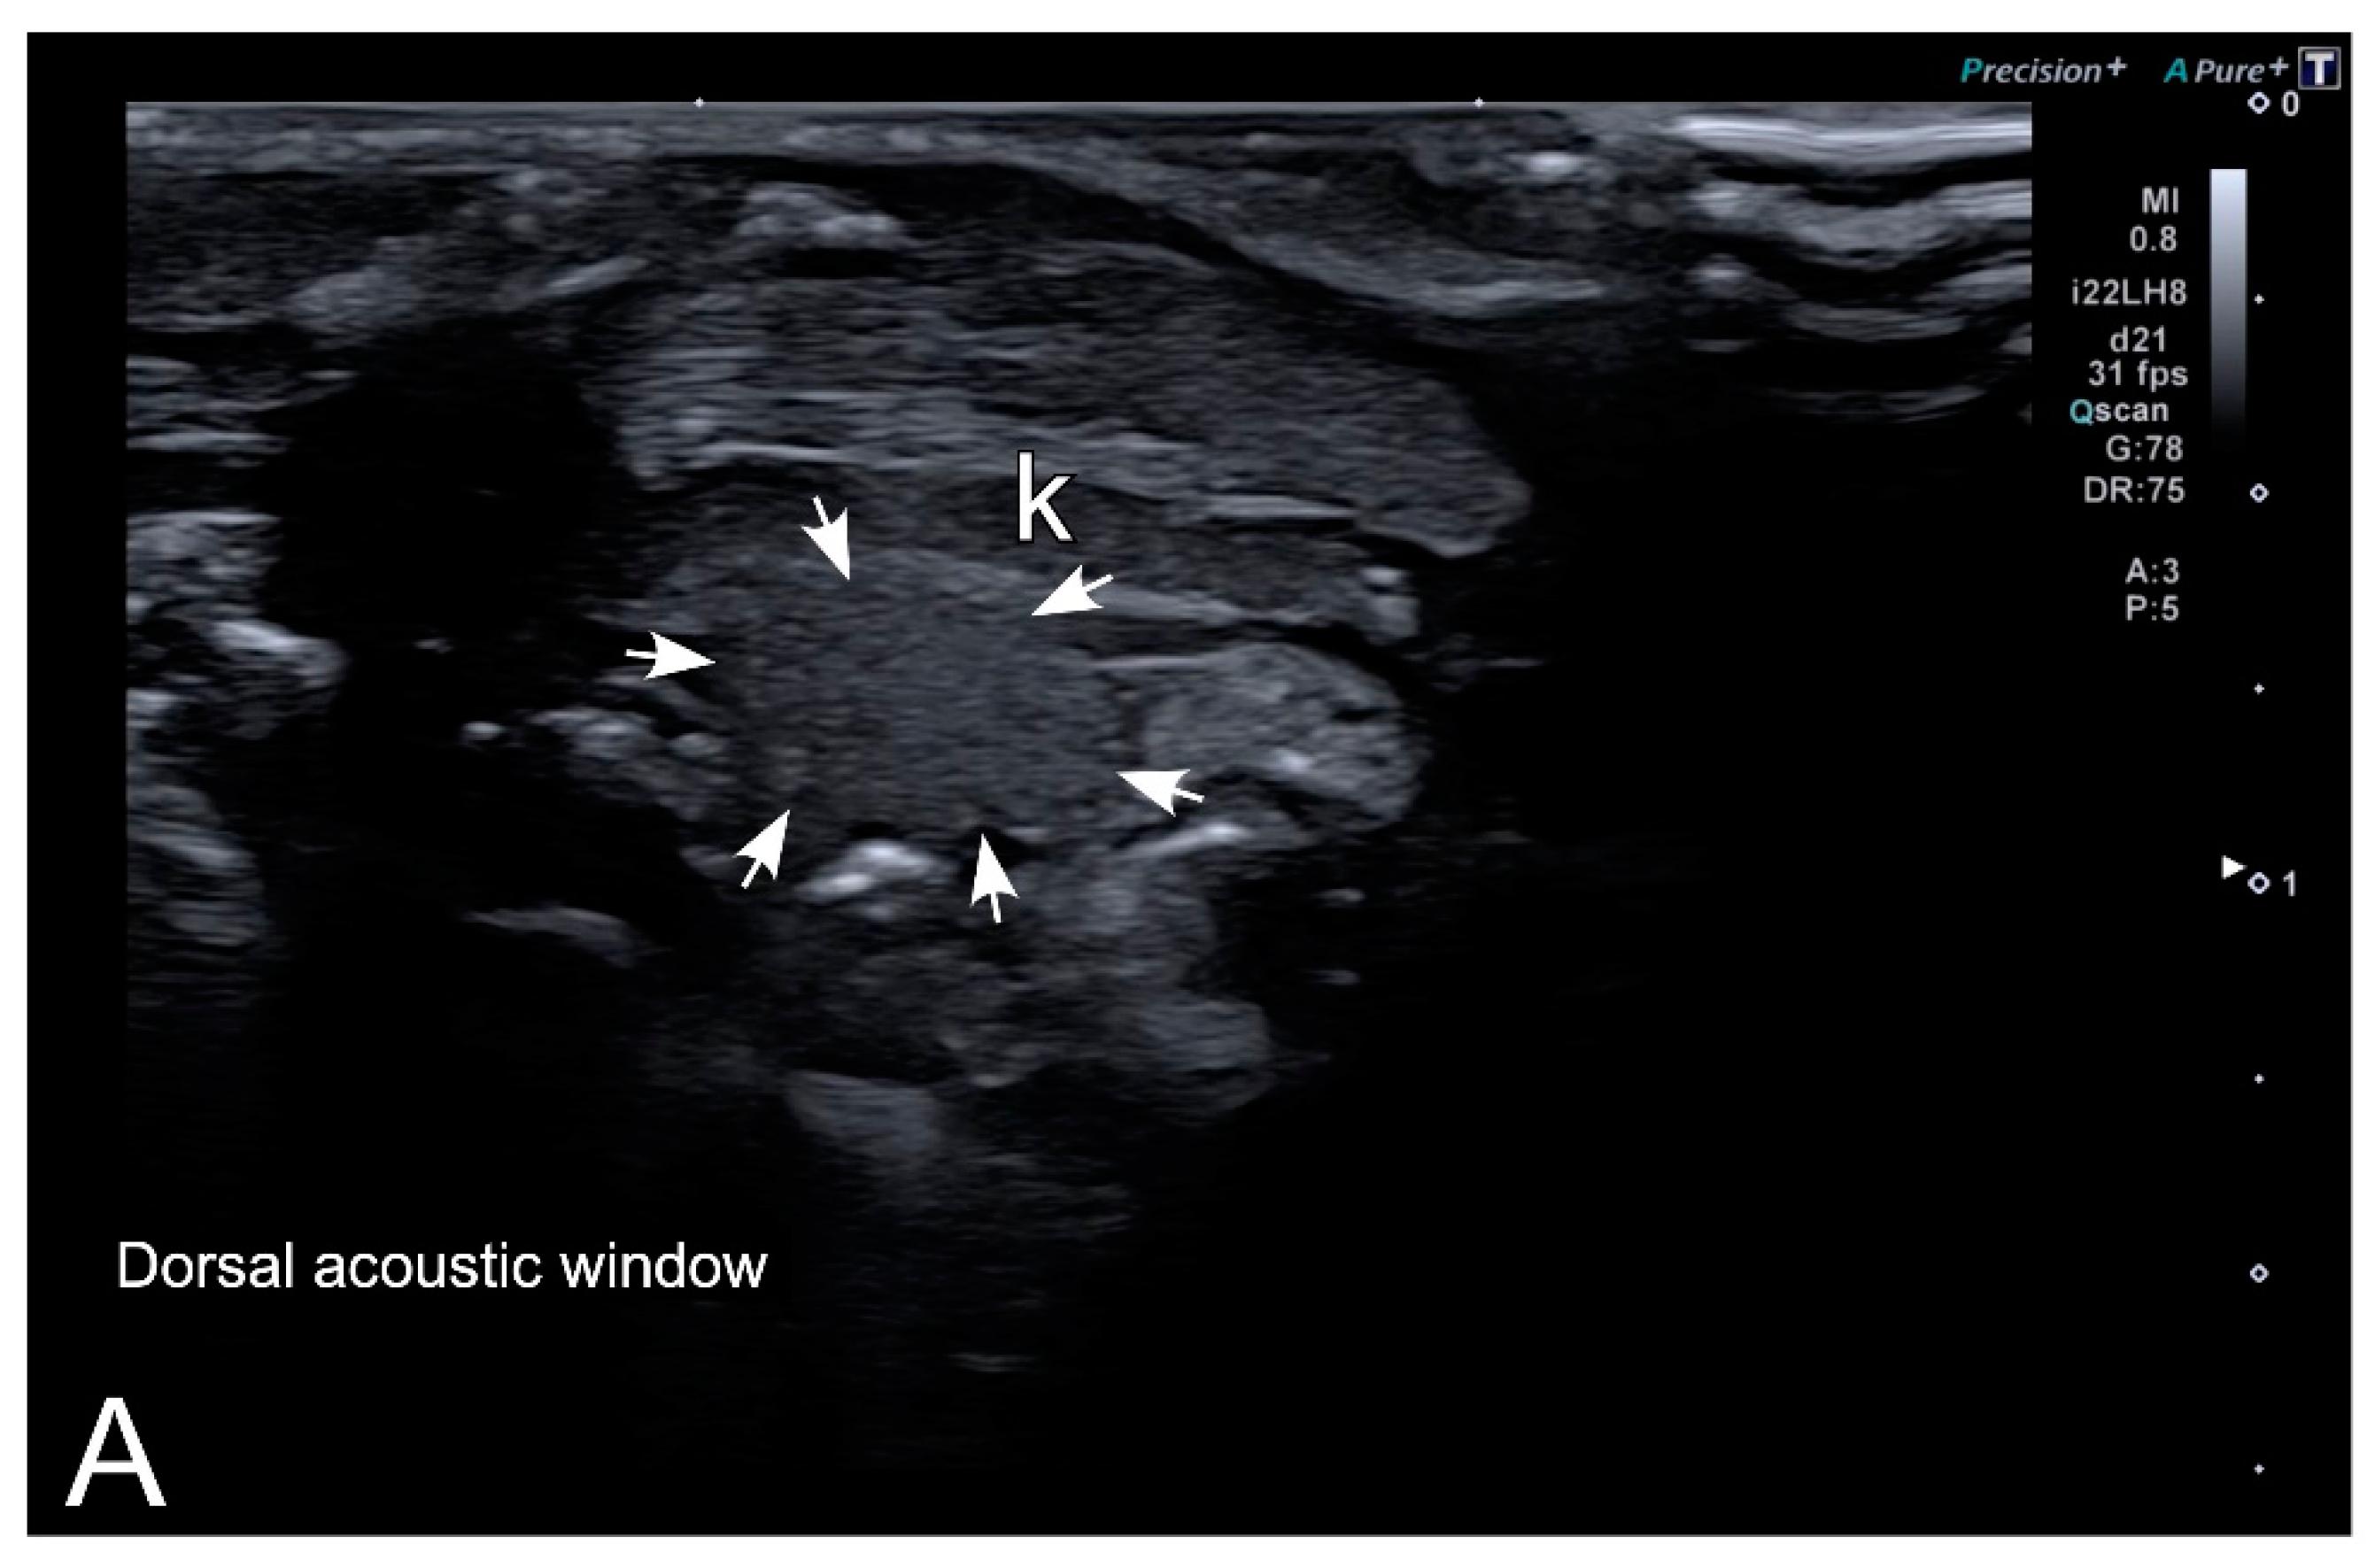

Figure 5. HR-US images of a female Xenopus laevis in the longitudinal plane using ventral (A) and dorsal (B) acoustic windows. Although the complex of follicles is clearly identified in both, the ventral acoustic window was considered more adequate for the examination of female gonads. Nevertheless, the kidney (k) was better identified using the dorsal acoustic window. |

Figure 7. Representative HR-US images of Kaloula pulchra (A) and Xenopus laevis (B) males obtained in the longitudinal plane using a dorsal acoustic window. The testes (delimited by arrows) appeared as structures with oval morphology, mid echogenicity and homogenous echotexture. Testes were located just ventral or ventrolateral of the ipsilateral kidney (k). |